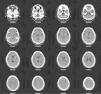

Entre las exploraciones complementarias, se solicitaron una RM y un SPECT para ver si hay hallazgos anatómicos cerebrales de esquizofrenia tipo II de Crow15. Ya en 2005 a la paciente le había sido realizada una resonancia magnética cerebral sin que se encontraran alteraciones significativas. En la RM realizada en 2010 destacaba la presencia de atrofia cerebral leve de predominio frontal (fig. 3), mientras que en el SPECT se observaba una hipoperfusión temporal bilateral (fig. 4).

Sólo tras muchos años de enfermedad, como conclusión de la evolución clínica de la paciente, los resultados obtenidos en las pruebas psicométricas descritas, y los hallazgos de las dos pruebas de neuroimagen realizadas, llegamos al convencimiento de que todo apoya el diagnóstico de esquizofrenia simple17.

Aunque no siempre, en varios estudios sobre las anomalías neuromorfológicas de pacientes con diagnóstico de esquizofrenia simple, se encuentran anomalías características de otros subtipos de esquizofrenia, como mayor volumen ventricular y del espacio subaracnoideo, así como más alteraciones del desarrollo cerebral23–25. Estudios sobre potenciales evocados visuales muestran alteraciones en varios subtipos de pacientes esquizofrénicos, incluidos aquellos que recibieron el diagnóstico de esquizofrenia simple26. Las pruebas de neuroimagen funcional, como el SPECT, pueden mostrar déficit de perfusión de las regiones frontales, asociados a aspectos de la esquizofrenia como la cronicidad, la presencia de un síndrome clínico negativo y deterioro cognitivo17. Esta hipoperfusión de la materia gris prefrontal también ha sido encontrada en estudios más recientes como el de Suzuki27.

Tratándose de un trastorno que, psicopatológicamente hablando, puede presentarse con un bajo perfil sintomático (en el caso que describimos, los resultados del test de personalidad oscilan desde lo muy patológico, en 2005, y la normalidad, en 2010), y la utilización de pruebas de deterioro neuropsicológico y funcional, así como pruebas de neuroimagen funcional, pueden ser de gran utilidad para diagnosticarlo18.